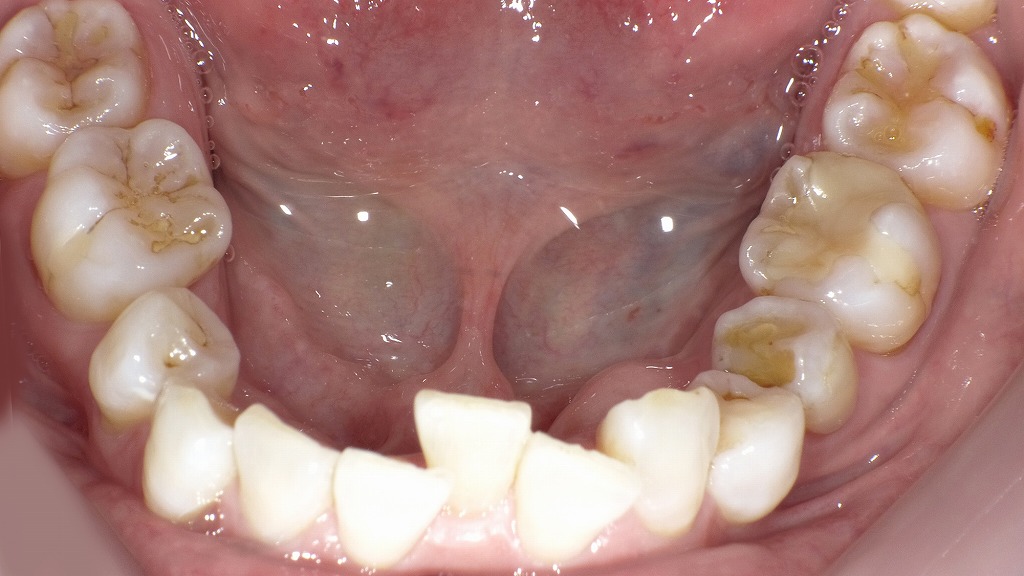

下記の口腔内写真は下顎前歯に**叢生(歯の重なり)**があり、歯間の清掃がやや難しい状態です。プラークがたまりやすく、歯石や歯肉炎の原因になることがあります。